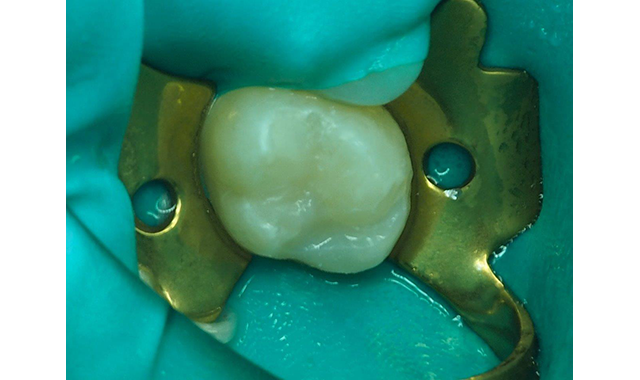

Fig. 1 The pre-operative view, with deep pit caries in newly erupted maxillary second molar.

Consequently, the patient still had carious maxillary second molars to be restored (Fig. 1). She was concerned the restorations would be “painful” postoperatively and worried about the consequences of the planned posterior composite restorations.

Fig. 2 Rubber dam placed post-anesthesia and the molar prepared with #330 carbide bur in high-speed handpiece with copious water spray.

After placement of the rubber dam, the preparation was performed with a high-speed handpiece using sufficient water spray and the carious dentin exposed (Fig. 2). The carious infected dentin was removed with a #4 round bur (keeping the dentin moist) in a slow-speed handpiece and with judicious use of a sharp spoon excavator (Fig. 3).